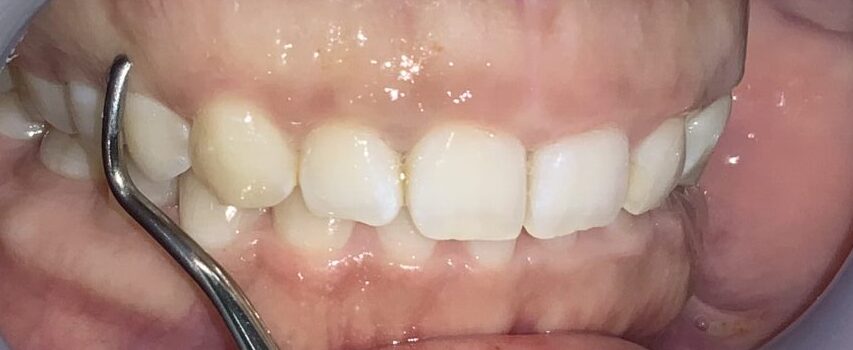

患者様のOKが出たので、すべての歯の治療を行いました。

歯ぐきの面積が少なくなって、笑った時の歯ぐきが見えなくなり、歯の形も、歯ぐきの形も綺麗に改善しました。

歯ぐきが一部黒ずんでいる部分は、数日で改善するのでご安心ください。